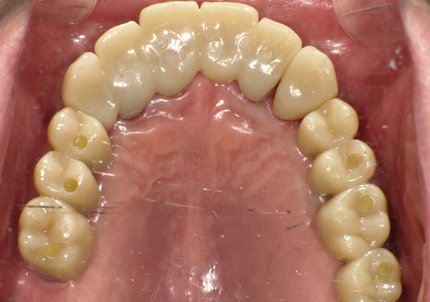

1.初診時口腔内写真(2014年6月)

2.治療終了(2016年6月)

・上顎補綴物再製

・右下2本インプラント

・左下ジルコニアクラウンブリッジ

10.口腔内写真(2022年2月)

特に問題無く経過はとても良いです。

患者様ご本人も「良く咬めてとても良い」と満足されています。

11.口腔内写真(2025年6月)

右下2本初診より9年経過、左下3本埋入後4年経過、ともに経過良好。